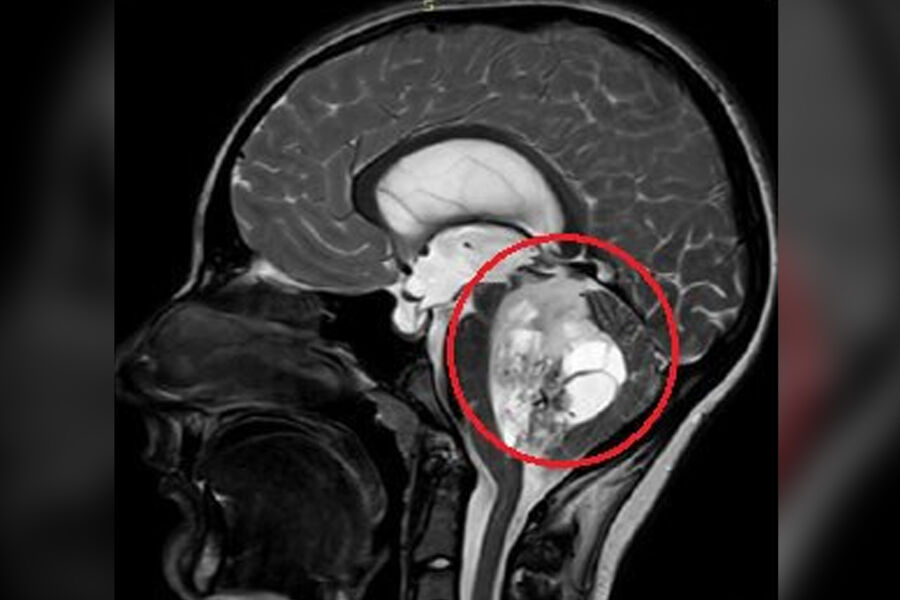

Врачи Детского центра имени Рошаля спасли 15-летнего подростка, удалив ему объемное новообразование в мозге. Об этом сообщили в пресс-службе медицинского учреждения.

По словам медиков, юноша жаловался на постоянную тошноту и рвоту, которые не удавалось купировать консервативными методами. На обследовании специалисты обнаружили пятисантиметровую опухоль в задней черепной ямке. По словам врачей, ее дальнейший рост мог привести к нарушению жизненно важных функций мальчика.

«Сложность данного случая заключалась в том, что опухоль росла из области, которая отвечает за жизненно важные функции - любое, даже маленькое повреждение могли привести к тяжелым неврологическим осложнениям», — отметили нейрохирурги.